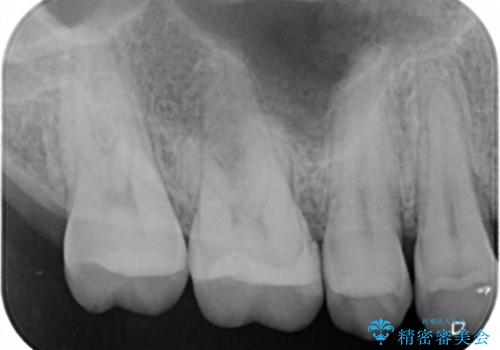

- 右上6番の虫歯治療を主訴に来院された患者様です。

切削量・形態を考慮し、セラミックインレーでの治療を計画しました。

保険の材料が劣化し中で虫歯が進行していたので、全て取り除いた上で形を整え型をとりインレーをセットしています。